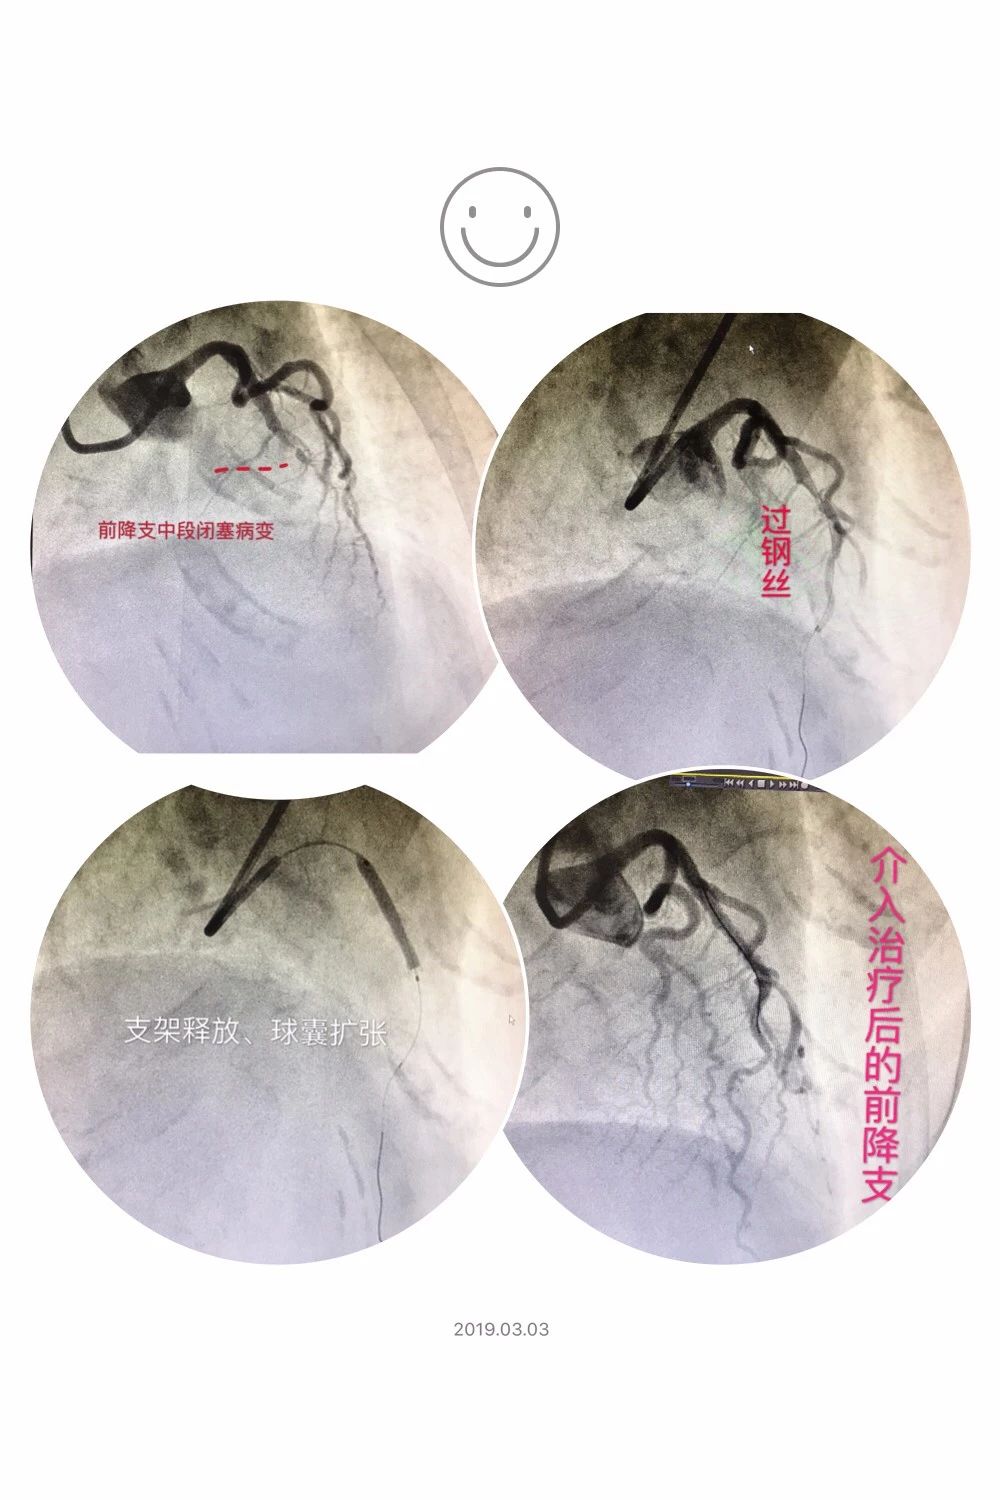

12时54分,患者安全抵达市胸痛中心,经心内科吴实正住院总医师充分向家属告知病情并获得家属同意后,立即开通绿色通道双绕行(即绕行急诊科及心内科病房)直接将患者送入导管室,此时胸痛中心团队在导管室早已等候多时并做好相关准备。主任医师张惠琪、副主任医师廖成标、副主任医师乐建华、副主任医师张进鹏、副主任医师黄少伦等专家团队在术前充分探讨并制定各种应对策略为手术保驾护航,由副主任医师乐建华、主治医师吴实正紧急仔细地为患者成功行介入手术治疗。该患者D2B(Door to Balloon,指患者入医院大门口到球囊扩张)时间仅耗时23分钟,这一数值再次刷新了市胸痛中心曾经创造的27分钟记录(2018年8月21日,救治急性心肌梗死患者实施急诊PCI耗时27分钟)。

患者术中冠脉造影图

患者术中生命体征平稳,术后胸痛立即缓解,随后被送到心血管内科专科病房继续治疗,经医护团队精心治疗、悉心护理后于2月26日康复出院。